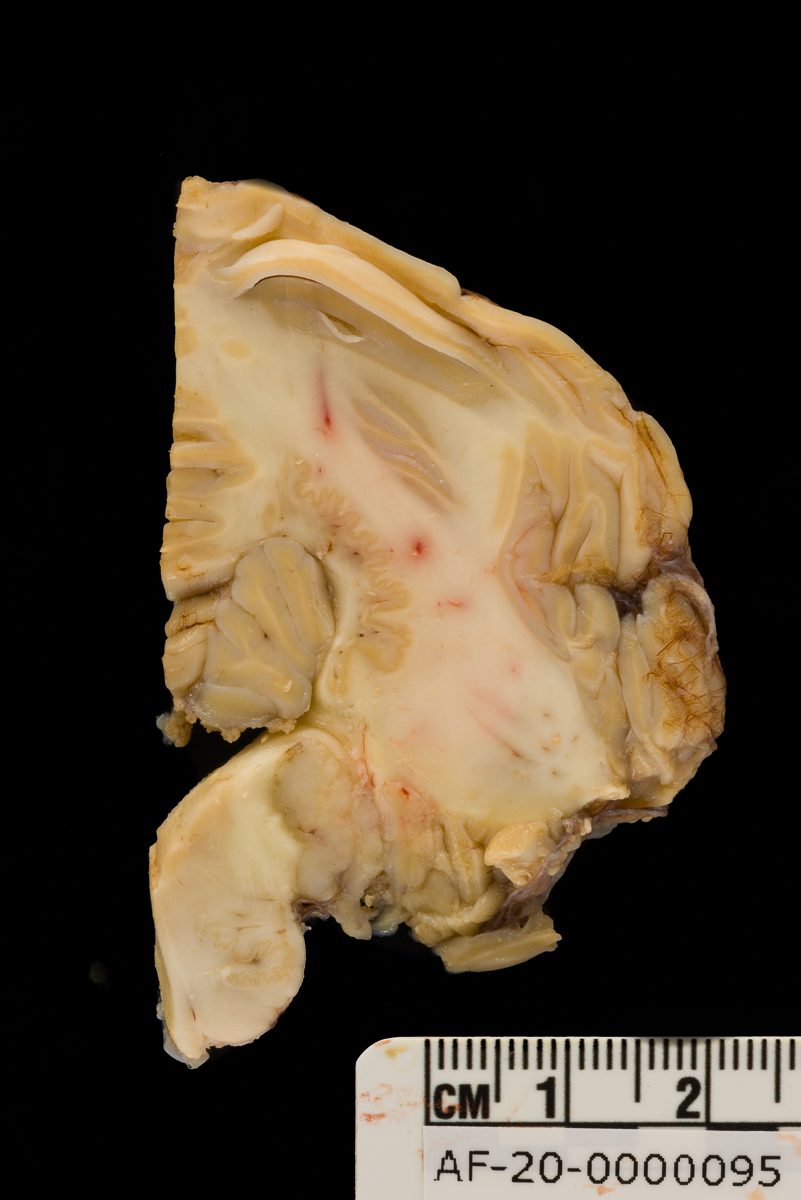

Case 5